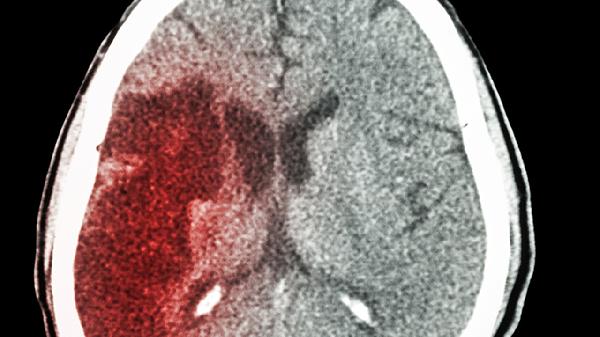

56岁大姐深夜突发脑梗离世,医生:5种食物吃太多,最易堵塞血管

深夜的急诊室总是充满意外,56岁的李大姐没能挺过那个平常的夜晚。当救护车呼啸而至时,她的血管已经像年久失修的水管一样堵得严严实实。这不是偶然,而是日积月累的饮食"债台高筑"的结果。血管最怕的5种食物,你可能天天都在吃!